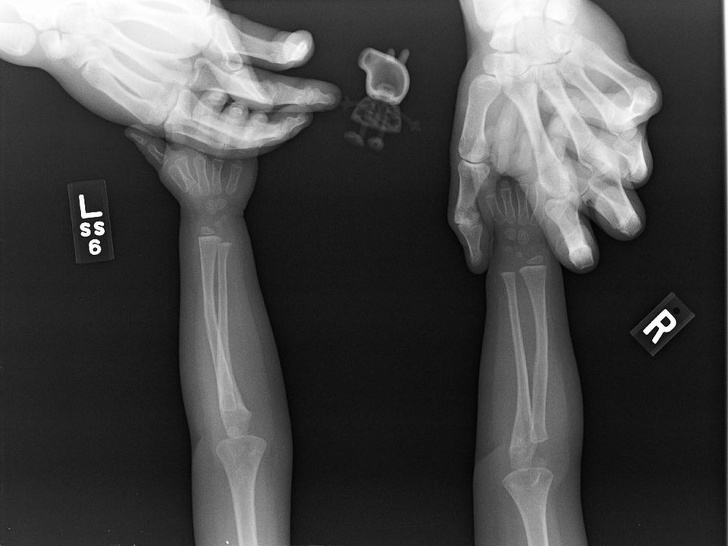

11. Так змінюється рука дитини з віком

20 знімків, які раніше бачили тільки рентгенологи. А тепер можете і ви

На місці деяких кісток спочатку розташовуються хрящі, які пізніше замінить кісткова тканина.